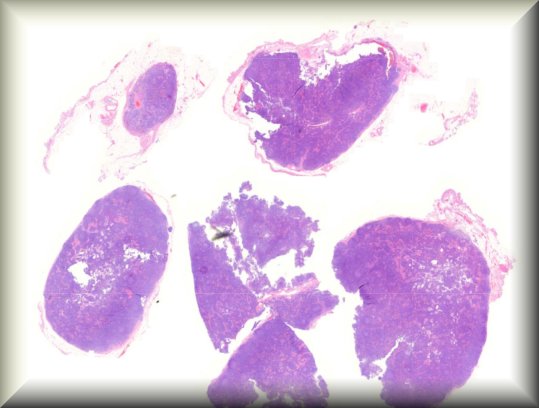

Dietmar Thal (Leuven): Eyeball resection for melanoma in an 83-year old male Alzheimer's disease patient |